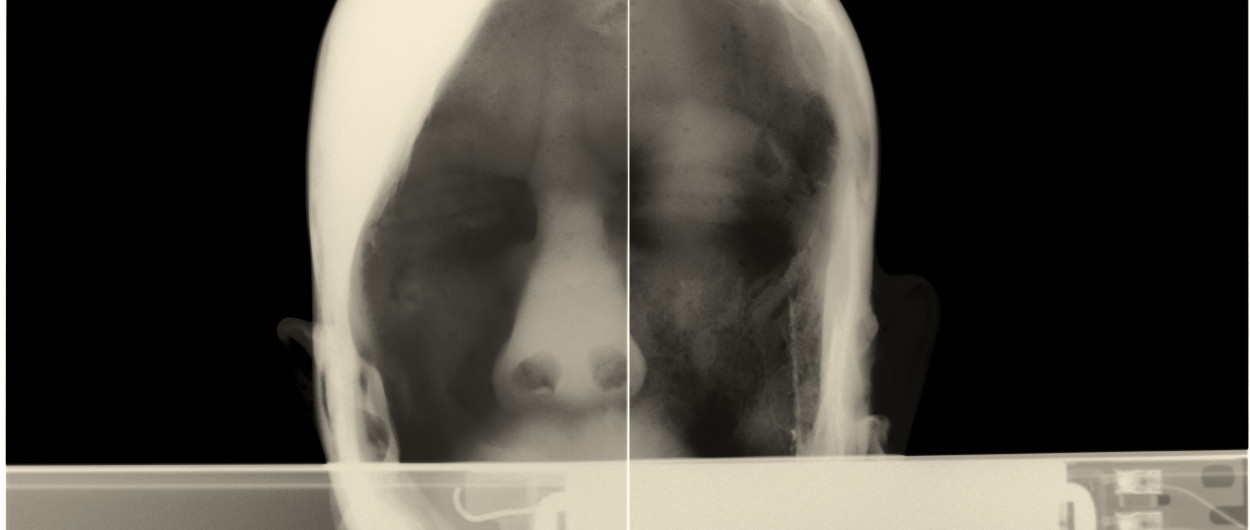

Artifacts of Evidence / Dokazno gradivo je prostorska instalacija umetniških del studia Paul O Robinson v dialogu s knjigo-artefaktom umetnice in oblikovalke Maje Licul. Preobraženim objektom in prostorom iz hiše Jožeta Plečnika so sopostavljena dela, ki izhajajo iz kontinuiranega raziskovanja interierjev in eksterierjev v Sloveniji in Italiji – v slednji natančneje v muzeju Fortuny v Benetkah. Postavitev se ukvarja z vprašanji stalnosti in minljivosti ter preoblikovanja konvencionalnih znakov v nove snovne oblike. Rentgenska dokumentacija je pretvorjena v slikarske in kiparske forme, pri čemer se skrita vsebina razgrinja v nove prostorske strukture.